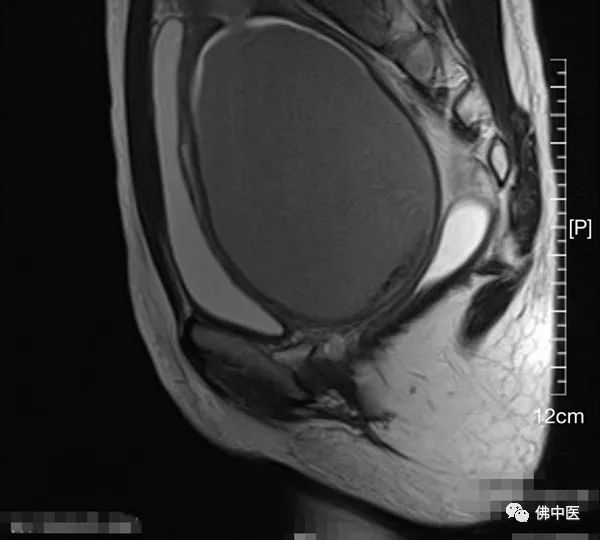

我院MRI检查显示为先天性阴道闭锁

我院MRI检查显示积血形成肿块

术前MRI提示,患儿双侧附件区卵巢形态及信号未见异常,子宫及阴道体积增大,子宫腔及阴道内积血,结合病史,符合先天性阴道闭锁。由于女性生殖器官发育异常多合并宫颈闭锁、泌尿系统发育异常,手术部位解剖结构术前难以完全明确,从而为手术增加了不少难度。因此,术前游哲辉与罗健主治中医师、韦燕医生等在科内做了详细的讨论交流,并制定手术方案和设计术后模具。